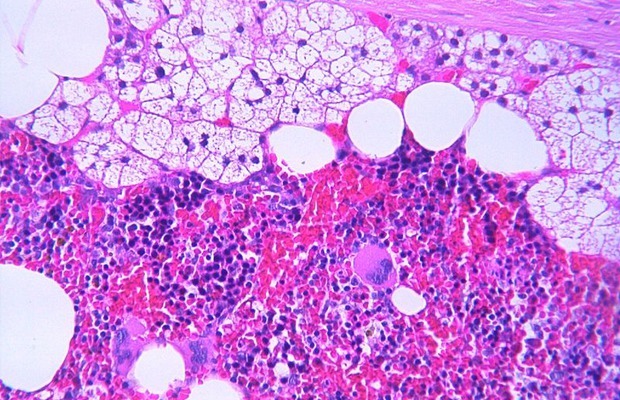

Окрашивание гематоксилином и эозином

Биологическая ткань на препаратах получается недостаточно контрастной. Окрашивание придает ей требуемый контраст и выделяет интересующие особенности.

Окрашивание гематоксилином и эозином считается рутинной процедурой для оценки стекол при световой микроскопии. В синий цвет окрашиваются ядра клеток и некоторые другие объекты, а затем водным или спиртовым раствором эозина в разные оттенки красного, розового и оранжевого окрашиваются цитоплазма и эозинофильные структуры.